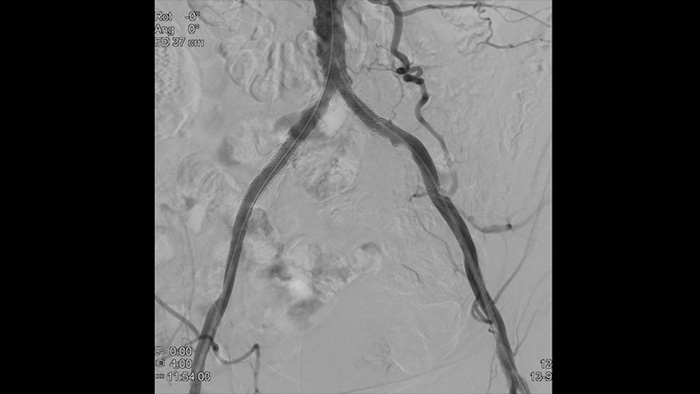

Our Vascular suite provides workflow options, dedicated interventional tools, and a broad selection of advanced vascular devices to improve procedural efficiency and redefine outcomes for your patients with aortic disease. They support each step of your procedure – as you decide, guide, treat and confirm treatment results.

With Philips Azurion a breakthrough in workflow improvement has been realized, resulting in proven efficiency. With the ever growing number of patients with aortic disease, Azurion offers a number of workflow innovations designed to help vascular teams work efficiently and consistently, while maintaining a single-minded focus on the patient and managing radiation dose during interventions.